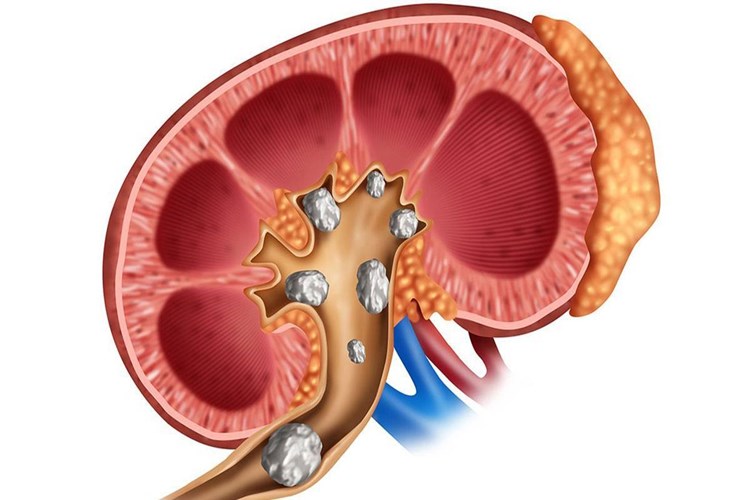

Böbrek taşı düşürme sürecinde, bazı durumlarda idrar yolunda

bir akıntı meydana gelebilir. Böbrek taşları, böbreklerde oluşur ve idrar yolu

boyunca idrar torbasına kadar ilerleyerek vücuttan atılır. Bu süreç sırasında,

taşın idrar yolunu tıkaması veya tahriş etmesi nedeniyle idrarda kan

görülebilir ve bu da idrarda bir akıntıya neden olabilir.